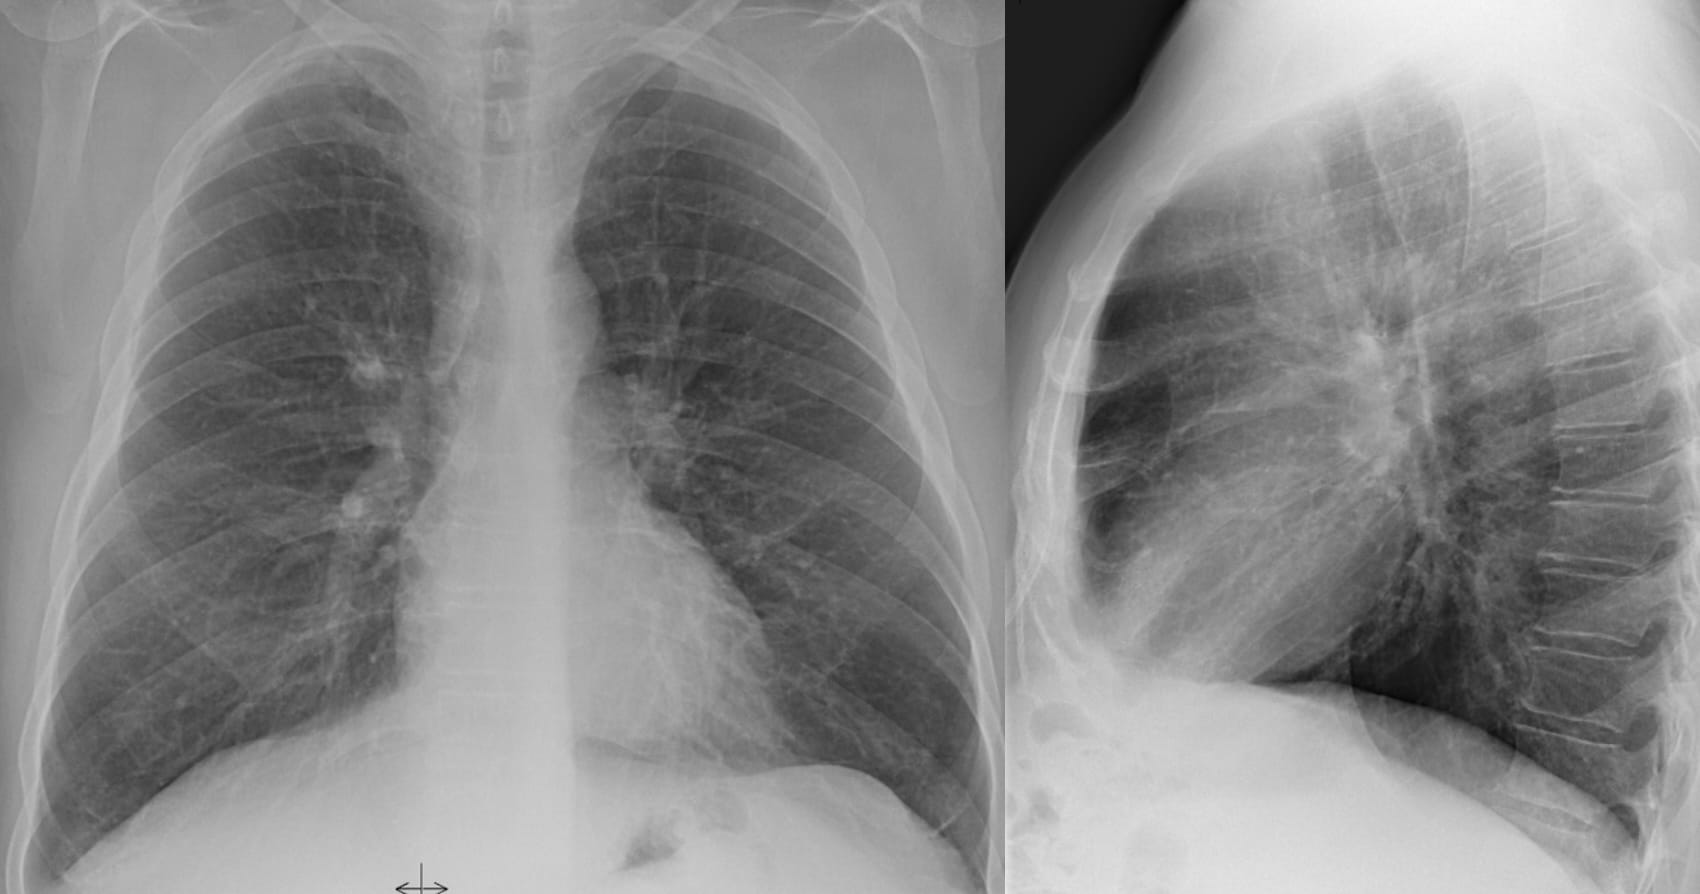

Another Aunt Minnie

It’s a matter of how many I put there with my macrophage spray can…